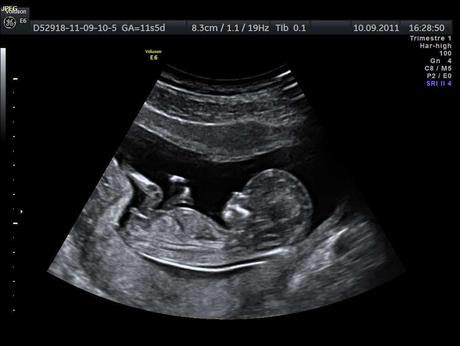

La plupart des centres d »échographie prénatale proposent des échos 3D aujourd’hui. L’échographie est une technique d’imagerie en coupes non irradiante basée sur les ultra-sons, elle permet de voir comment évolue le bébé durant la grossesse et prévenir les pathologies.

Les échographies proposées, de 20 minutes à une heure, sont réalisés par des professionnels (ce ne sont pas forcément des médecins) et présentent bébé et permet de le voir évoluer dans le ventre de maman.

Ce sont pas des échographies médicales et ne remplacent donc pas le suivi avec un médecin. Ceci est plus pour les parents qui veulent voir bébé en images avant l’accouchement.

N’oubliez pas de présenter votre dossier médical de grossesse à chaque rendez-vous médical et de demander un souvenir en 3D.